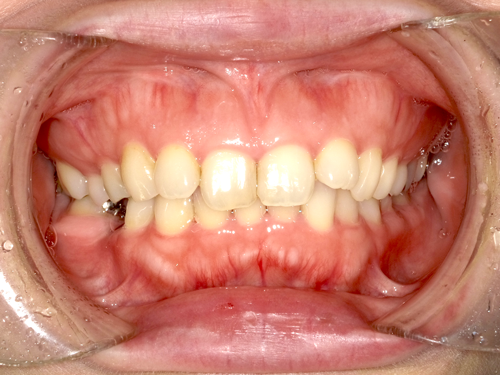

インプラントは、審美性の高い素材を使用でき、自然な仕上がりを実現可能です。ほり歯科・矯正歯科中央林間では、精密性の高い治療により、より美しい仕上がりを目指しています。